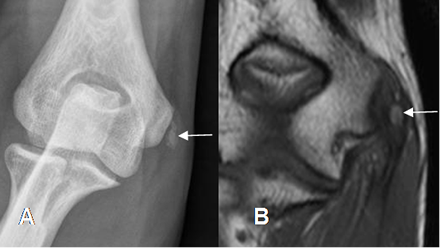

Con la Rx simple, puede encontrarse calcificación adyacente al epicóndilo medial, en

los casos crónicos. (Fig 46).

Fig 46. Epicondilitis medial.

A: Rx AP y B: RM coronal en T1. Calcificación sobre el origen de los tendones flexores, por tendinitis crónica.